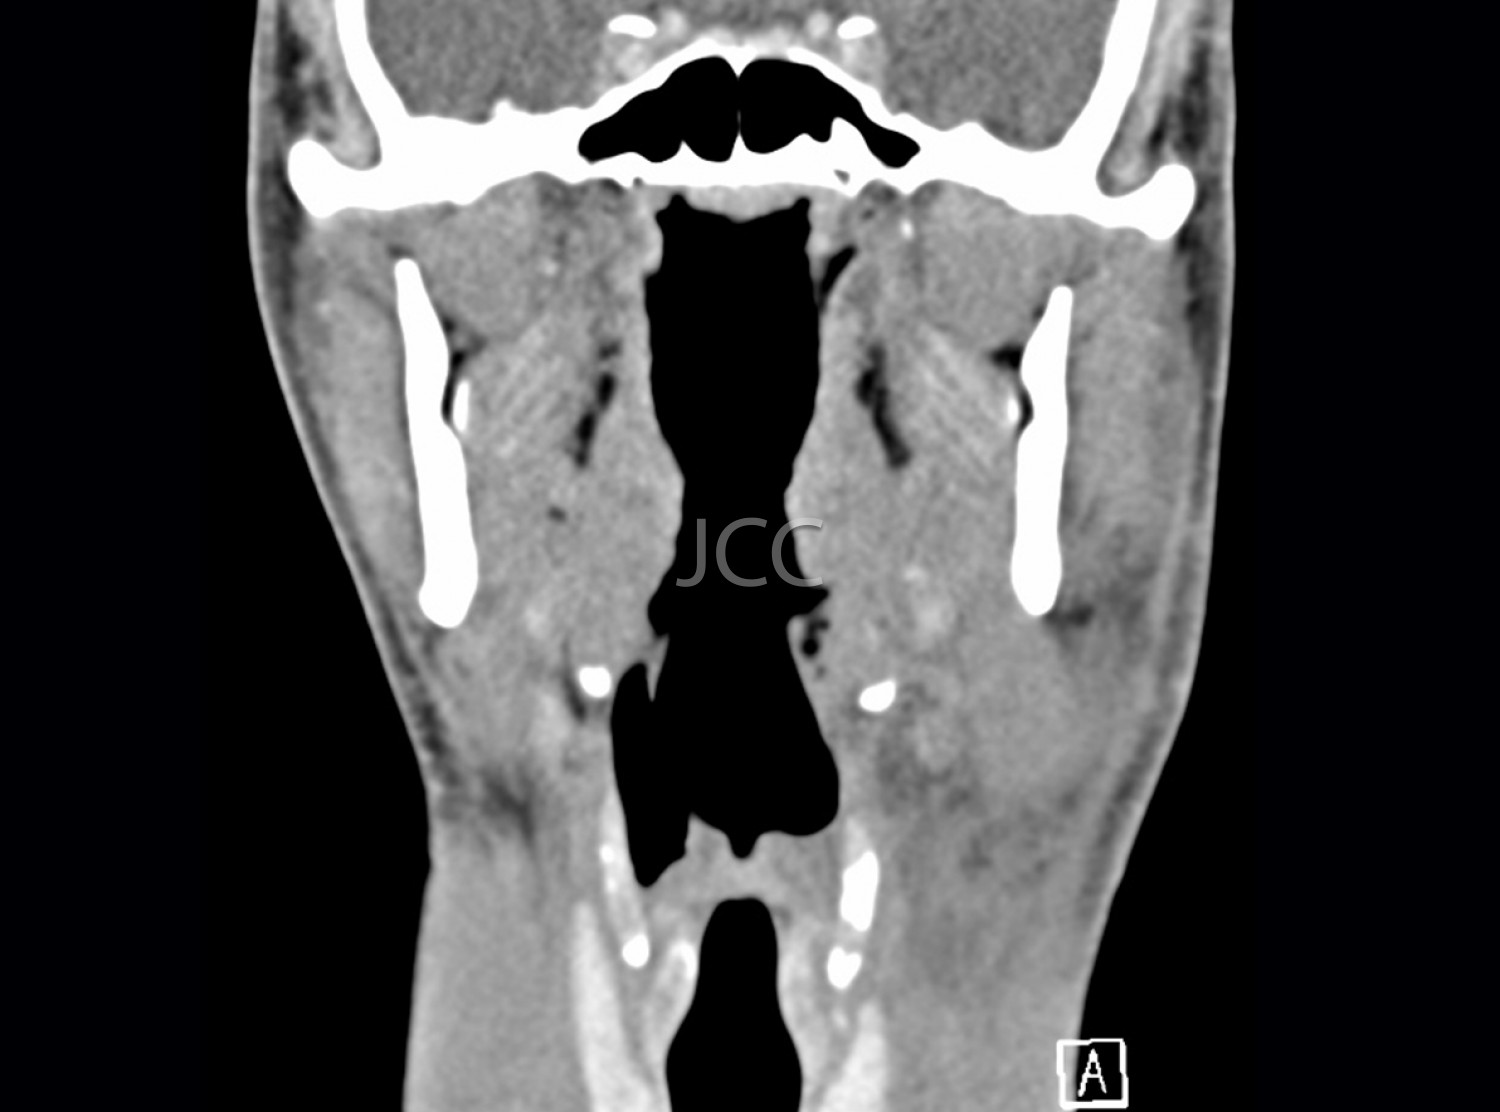

Tomografia Axial Computorizada - TAC Cavum

A Tomografia Axial Computorizada (TAC) - Dupla Energia - 256 cortes é uma técnica de diagnóstico que permite a avaliação de várias partes do corpo humano, incluindo pulmões, fígado, pâncreas, rins, coração, estruturas vasculares e estruturas ósseas.